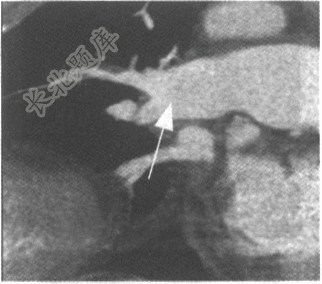

- 单项选择题男性患者,79岁。呼吸困难就诊。CT肺动脉造影如下图,可考虑为

A、慢性肺动脉栓塞

B、肺动脉高压

C、急性肺动脉栓塞

D、肺动脉狭窄

E、肺动脉损伤